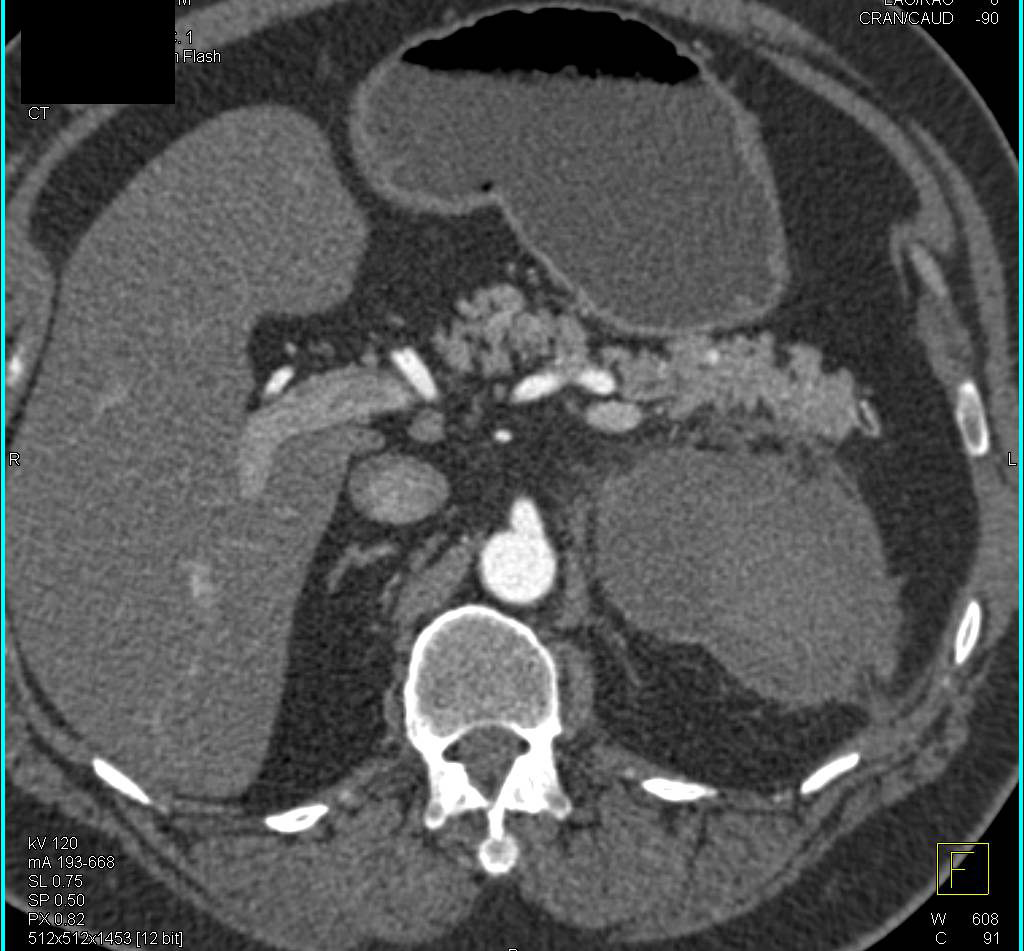

Sigmoid Volvulus